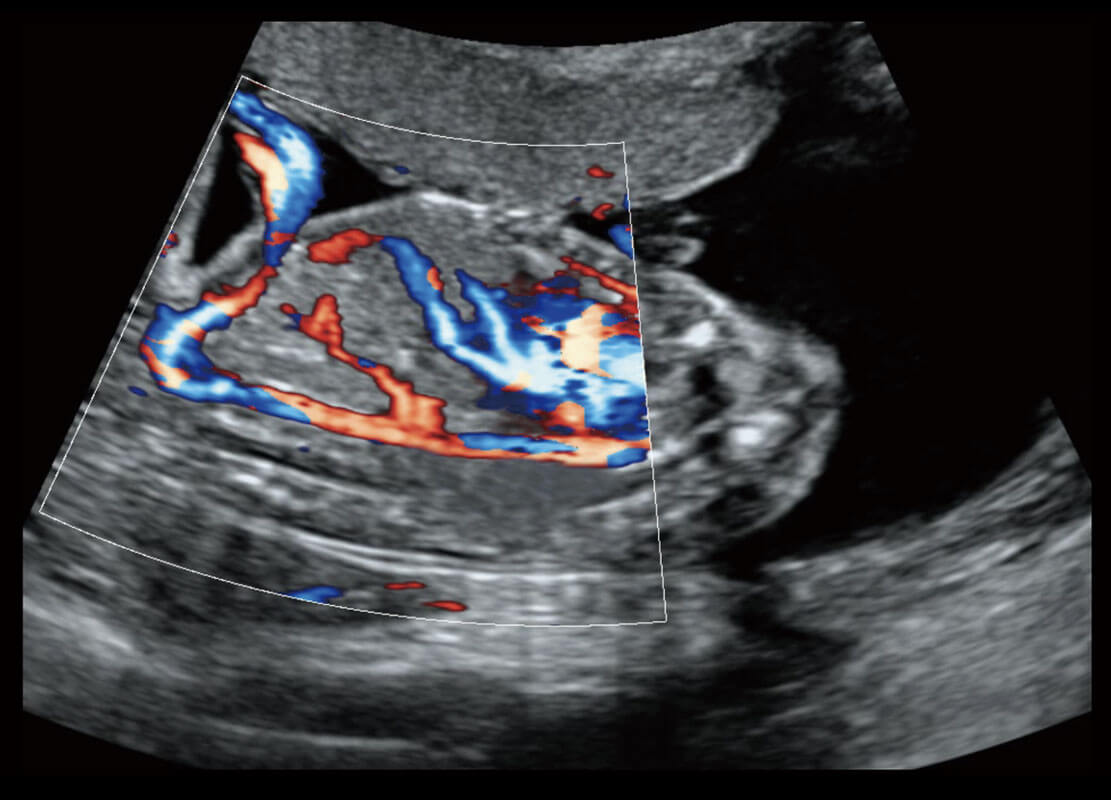

胎心筛查

P60搭载一系列胎儿心脏成像技术,实现精细的胎儿心脏评估。

• 四腔心血流

• 胎心容积成像